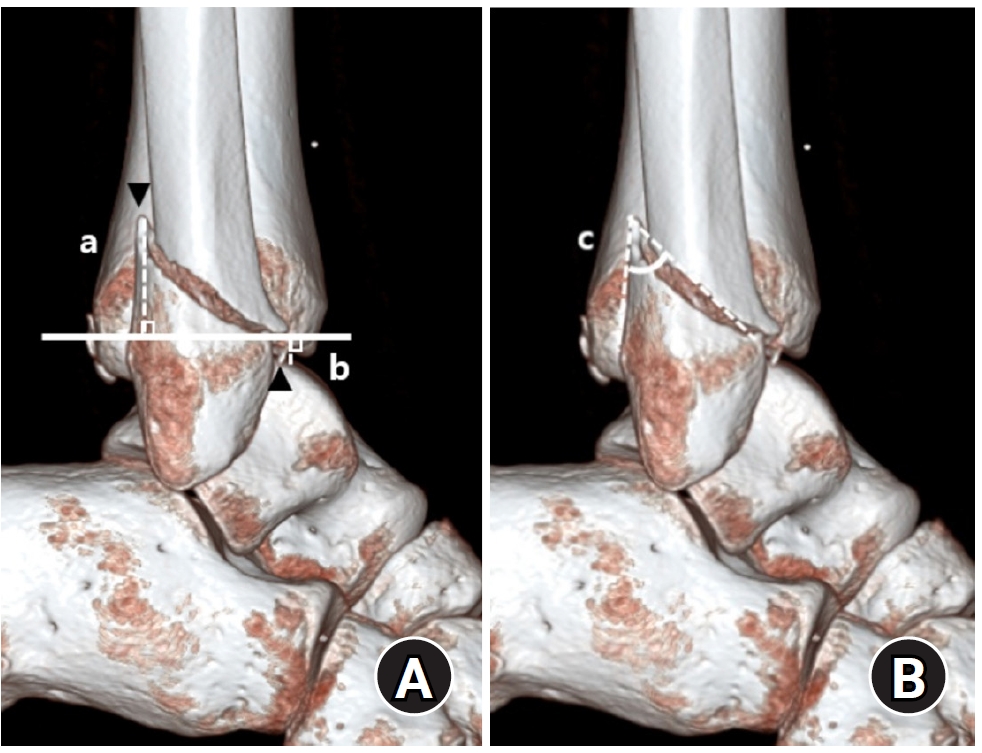

Demographic and clinical data were obtained from electronic medical records. Radiographic data were derived from 3D-CT scans. Radiographic analysis was performed using 3D-CT to assess the characteristics of both lateral and posterior malleolar fractures. Lateral malleolar fracture patterns were determined by measuring the vertical distance between the highest posterior cortex or lowest anterior cortex of the fracture and a line perpendicular to the tibial axis at the distal tibial articular surface. The angle between the posterior cortex of the lateral malleolus and the line connecting the anterior and posterior cortical points was defined as the fracture angle (Fig. 1).

Fig. 1.

Radiographic assessment of fracture characteristics. (A) Posterior height (a) and anterior height (b) represent the vertical distances from the highest point of the posterior cortex (▼) and the lowest point of the anterior cortex (▲) of the distal lateral fibula, respectively, to the line perpendicular to the tibial axis that intersects the distal tibial articular plafond. (B) The fracture angle (c) of the lateral malleolar fragment is defined as the angle between the posterior cortex of the lateral malleolus and the line connecting the anterior and posterior cortical points of the fracture.